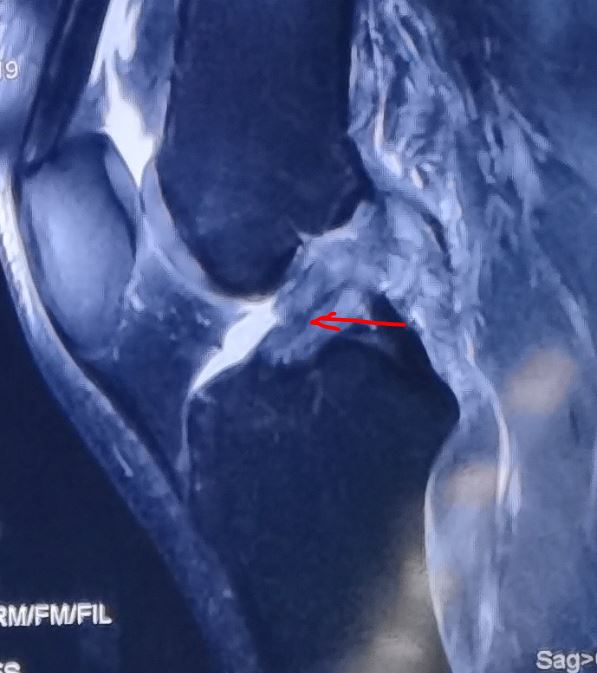

当然随着关节镜技术的发展及康复理念的发展,我们现在也主张在受伤1-2周内手术,因为我们发现前交叉韧带损伤后通过核磁MRI检查可以清晰发现韧带残端,这样早期手术可以很好的保留残端,这些残端的韧带具有血运营养、神经感受器,能够很好利于韧带生长及重返运动。

膝关节扭伤后核磁检查可以清楚的看到韧带残端,这样我们建议早期手术(时间越久韧带残端会吸收溶解),保留原有的一部分韧带。

膝关节扭伤后可以通过核磁MRI清晰显示前交叉韧带损伤,但韧带残端可见

因此,保残重建也是现在主流的手术方式!